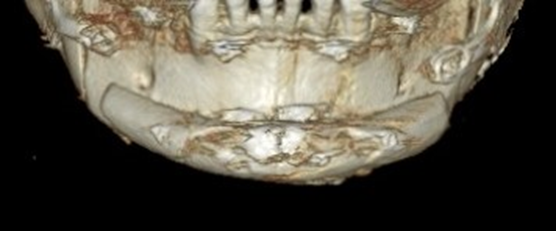

수술 3개월이 경과한 시점에 촬영한 CT입니다.

이식한 뼈는 자연스럽게 리모델링 되면서

거의 흡수 없이 잘 생착 된 상태로 회복하였습니다.

턱끝을 2단으로 절골하여 가운데 뼈를 제거하는 샌드위치 테크닉으로

턱끝의 길이를 5mm 줄이면서 앞으로 6mm 전진 시켰고,

단차가 생긴 뒷부분의 하악 하연을 매끄럽게 잘라낸 후 잘 다듬어서

앞턱 전체를 감싸면서 체부볼륨이 증가 될 수 있도록 이식하였습니다.